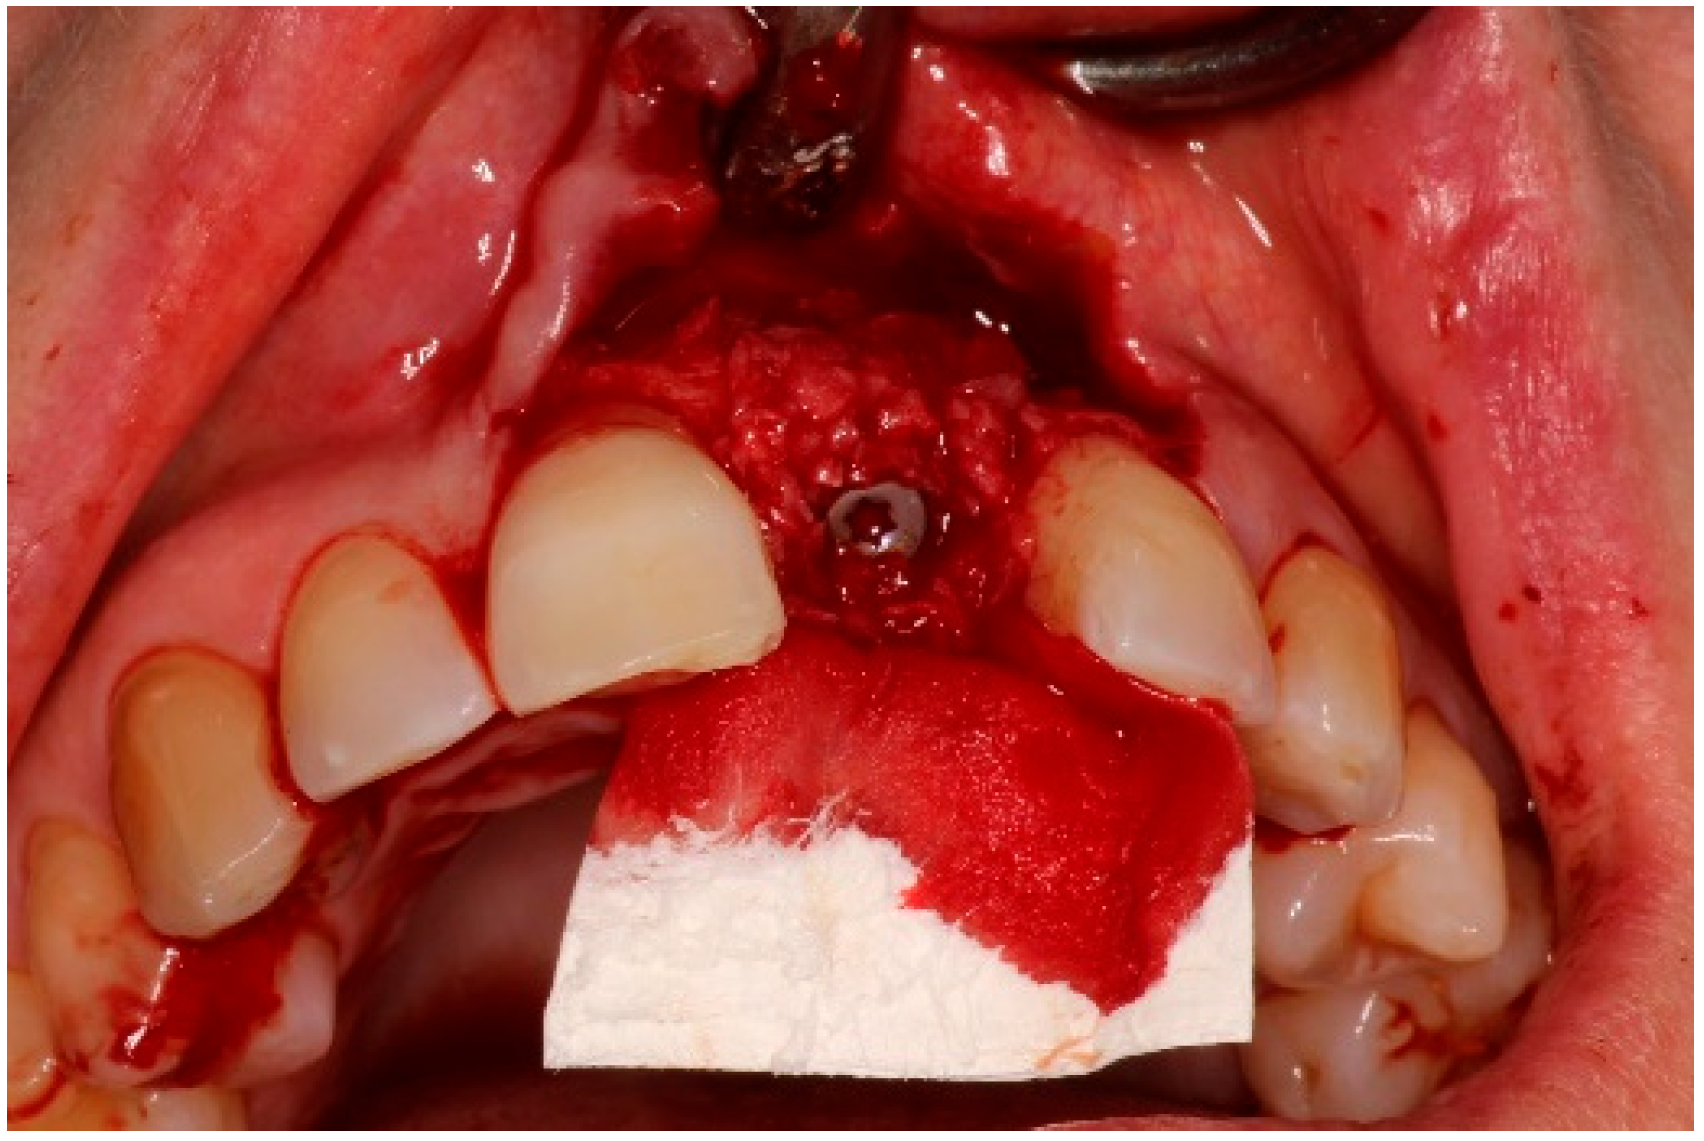

4. Timeline and Diagnostic Assessment

5. Therapeutic Intervention

5.3. Surgical Treatment